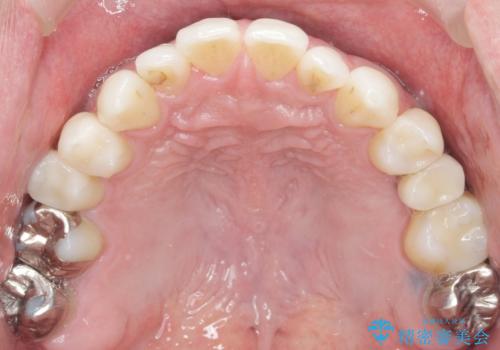

「違和感もなく、まるで自分の歯のようにしっかり咬めます!」と大変喜んで頂けました。

インプラントの種類:ストローマン BLT

被せ物の種類:オールセラミッククラウン スタンダード